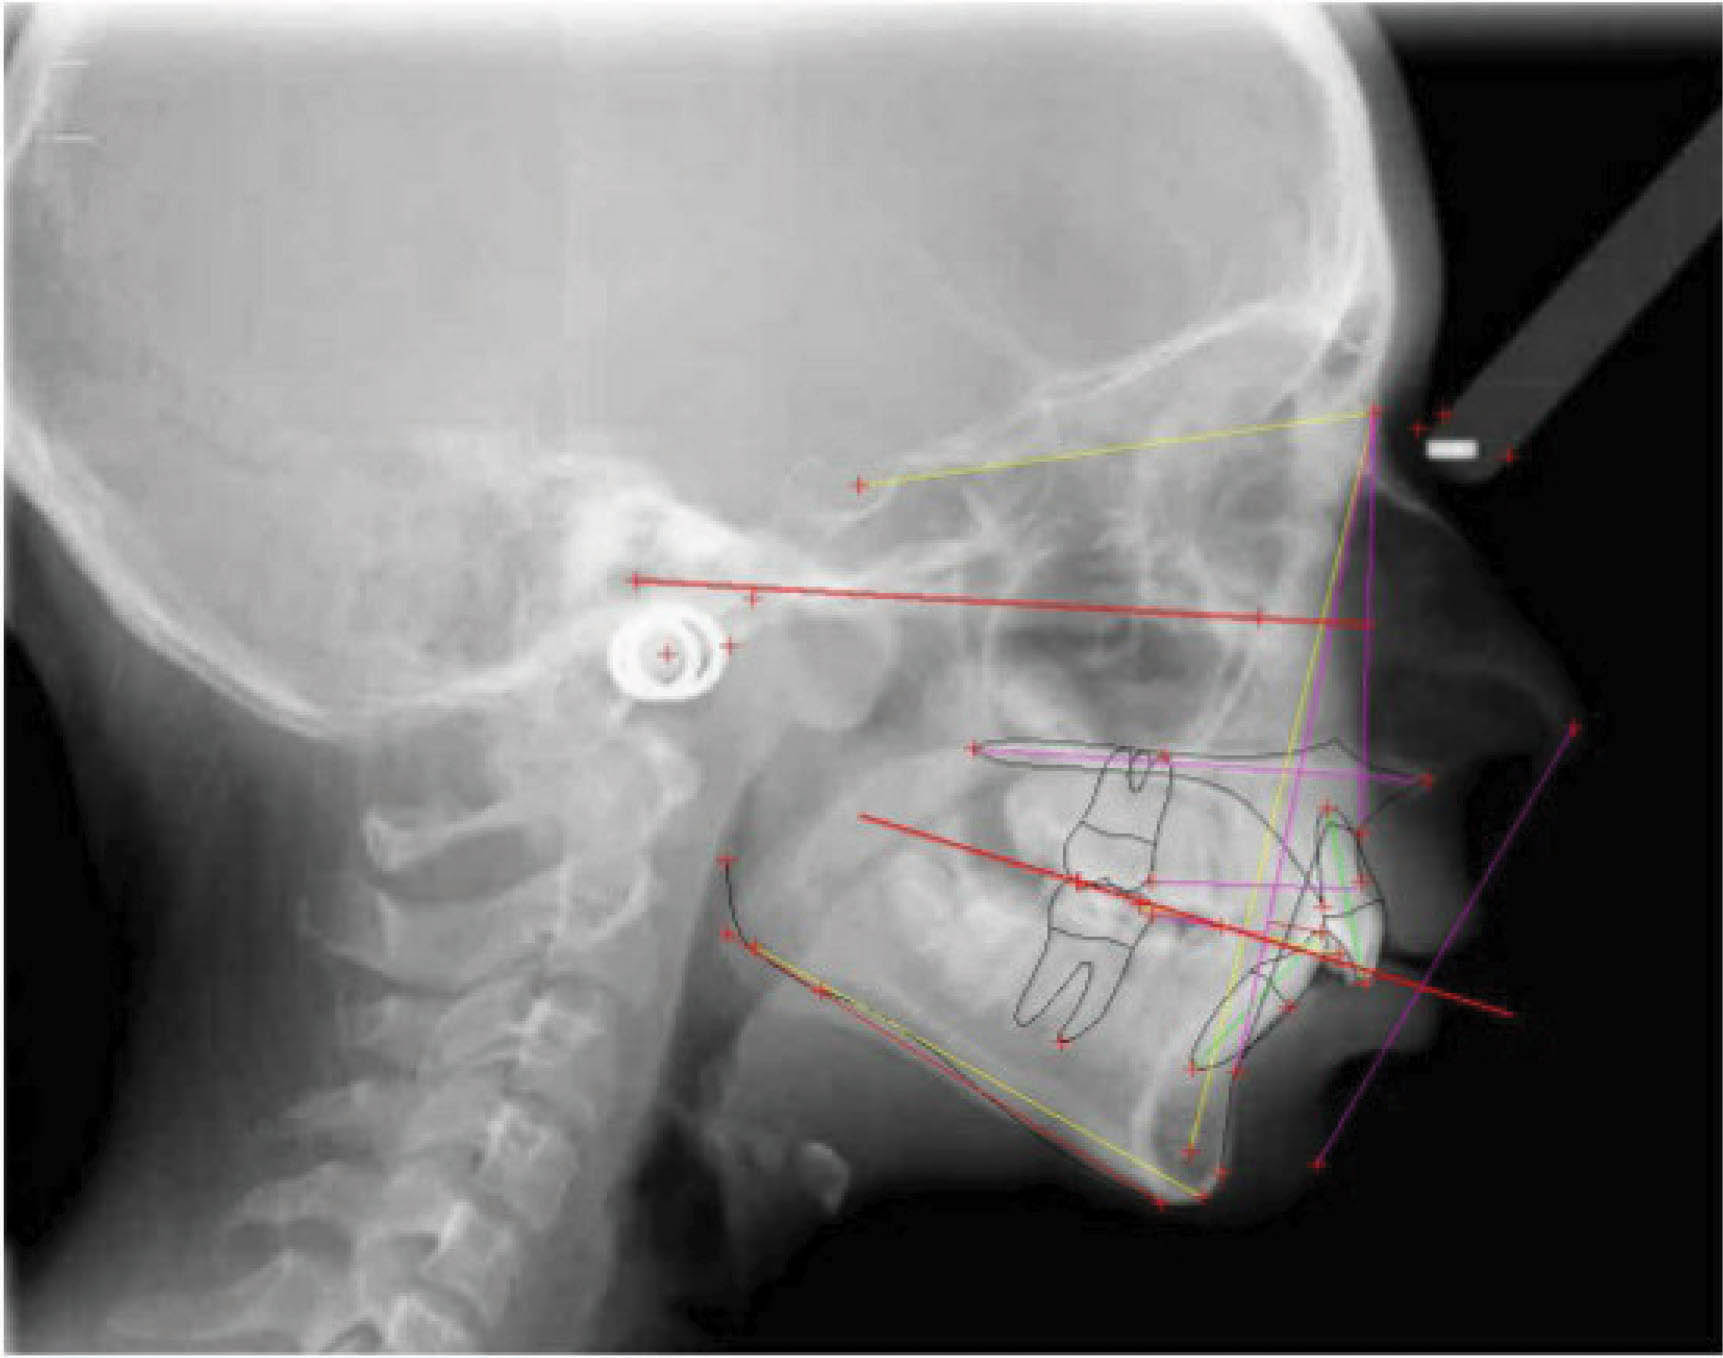

بیمار بعدی یک دختر ۱۶ ساله ClII/1 با اوربایت نرمال و اورجت زیاد است. کرادینگ مختصر دو فک دارد، قوس بالا تنگ، و پروفایل او طبیعی است (شکل 83-۶ الی 85-۶). در این بیمار از الاستیک کلاسII استفاده شده است. الگو اسکلتی طبیعی، رادیوگرافی لترال سفالومتری نشان دهنده دندانهای قدامی پروترود شده بالا با الگو طبیعی اسکلتی میباشد. رادیوگرافی OPG طبیعی است. قسمت بعُد افقی چک لیست را به این نحوه پر کردیم:

شکل 83-6

شکل 84-6